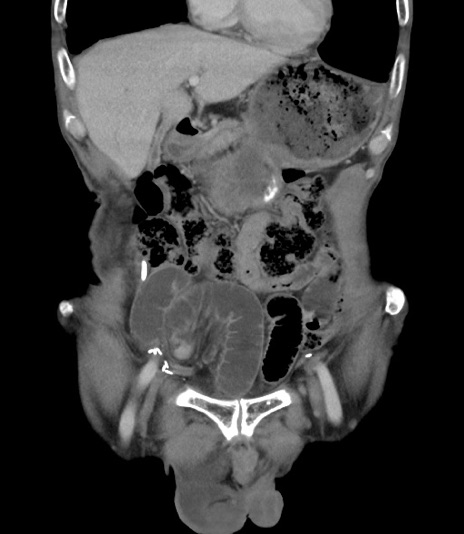

症例3(冠状断像)

症例

【症例】 70歳代男性

【主訴】右鼠径部腫瘤、疼痛

【現病歴】本日朝より上記主訴あり、受診。

【既往歴】膀胱癌にて膀胱全摘、両側尿管皮膚瘻

【データ】WBC 5600、CRP 0.56